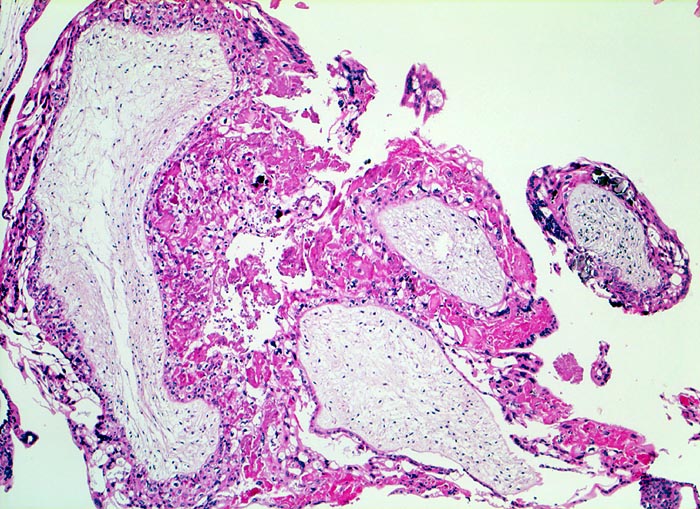

Makroskopisch ist die Plazenta deutlich grösser als erwartet für das Schwangerschaftsalter. Sie ist diffus von bis 2cm grossen Zottenblasen durchsetzt, welche nach Kollaps jedoch der makroskopischen Entdeckung entgehen können. Beim Aufschwemmen in Flüssigkeit entfalten sich die Blasen wieder. Mikroskopisch sind die Zotten aufgrund einer grobblasigen pseudozystischen Hohlraumbildung im Zottenstroma überwiegend grosskalibrig. Im Zottenstroma sind nur ganz vereinzelt Kapillaren nachweisbar. Im Gegensatz zu hydropisch geschwollenen Zotten im Sinne eines Regressionsphänomens zeigen die Zotten bei Blasenmole zusätzlich eine zirkumferentielle Hyperplasie von Synzytio- und Zytotrophoblast mit fakultativer Zellatypie. Bei herdförmiger Mole (> 3725) sind diese Veränderungen nur in einem Teil der Plazentarzotten ausgeprägt.

• Stark vergrösserte und verplumpte Plazentarzotten.

• Hydropisch umgewandeltes Zottenstroma ohne Gefässe mit Ausbildung von pseudozystischen Hohlräumen (Blasen)

• Trophoblastinklusionen und Kerntrümmer im Zottenstroma.

• Überschiessend proliferiertes Trophoblastepithel, teils in der gesamten Zirkumferenz der Zotten mit deutlichen Kernatypien. Kein Embryo.

• Blutkoagel